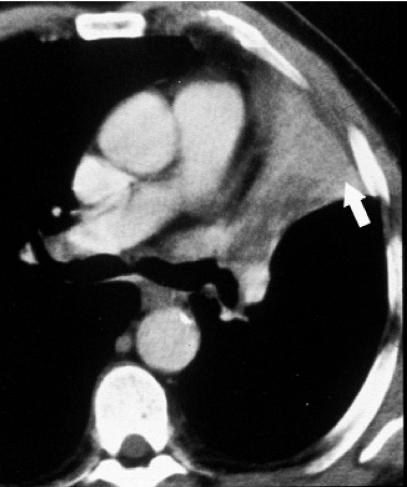

Effective treatment for carcinoma of the lung remains one of the biggest challenges in oncology. Radical radiotherapy may be a curative option for patients who are unsuitable for radical surgery either because of disease stage or because of co-morbidity. Long-term disease control with radical radiotherapy is disappointing with only about 6% of patients treated being alive at 5 years. Technological advances involved in the planning and delivery of radiotherapy may improve this. The advent of conformal radiotherapy, utilizing computed tomography and three-dimensional planning systems, allows much more accurate shaping of the radiation fields. This greater accuracy of target volume definition facilitates a reduction in the radiation dose to normal tissues, allowing for dose escalation to the tumour. Delineation of the target volume can be problematic. Conventional CT has limitations in term of distinguishing between benign and malignant tissues, e.g. the size criteria for involved lymph nodes. The oncologist uses a combination of radiological and clinical information when defining the target volume but their radiological interpretation of imaging is inferior to that of a radiologist. The Royal College of Radiologists (RCR) issued guidance in 2004 on the optimal imaging strategies for common cancers. These guidelines address issues regarding the localisation and staging of cancers and treatment planning, and also reporting and training. They recommend the development of closer links between radiologists and oncologists to optimise the interpretation of imaging and target volume definition. This article aims to briefly explain the planning process involved in irradiating lung cancers, highlight problematic areas and suggest ways in which co-operation with radiologists may improve the delivery of radiotherapy and therefore the treatment outcomes for this group of patients.

肺癌的有效治疗仍然是肿瘤学领域最大的挑战之一。对于因疾病分期或合并症而不适于根治性手术的患者,根治性放疗可能是一种治愈性选择。根治性放疗的长期疾病控制效果令人失望,接受治疗的患者中只有约6%能存活5年。放疗计划和实施过程中的技术进步可能会改善这一情况。适形放疗的出现,利用计算机断层扫描和三维计划系统,能够更精确地塑造辐射野。靶区定义的更高准确性有助于减少对正常组织的辐射剂量,从而可以提高肿瘤的照射剂量。靶区的勾画可能存在问题。传统CT在区分良性和恶性组织方面存在局限性,例如受累淋巴结的大小标准。肿瘤学家在定义靶区时会综合运用放射学和临床信息,但他们对影像的放射学解读不如放射科医生。英国皇家放射科医师学院(RCR)在2004年发布了关于常见癌症最佳影像策略的指南。这些指南涉及癌症的定位、分期和治疗计划等问题,以及报告和培训。它们建议放射科医生和肿瘤学家建立更紧密的联系,以优化影像解读和靶区定义。本文旨在简要解释肺癌放疗的计划过程,突出存在问题的领域,并提出与放射科医生合作可能改善放疗实施从而提高这类患者治疗效果的方法。